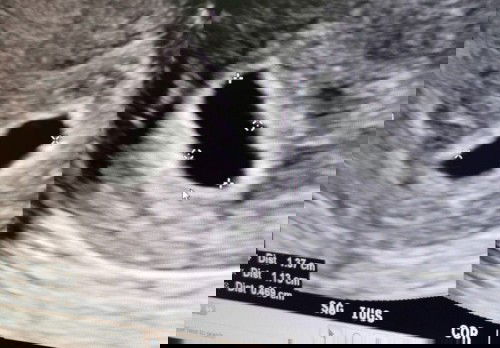

Week 5 day 5

Rushed to Kk's hospital after spotting for 2 days without cramping / pain, spent 6 hours there for all the investigations. Grateful that there is no miscarriage and no ectopic pregnancy. Based on my calculations from last menstrual date, I thought I should be at week 8.. But from the ultrasound, baby is just week 5 day 5, can only see gestational sac but cant see baby.. Anyone can't see baby too in week 5? #firstbaby #pregnancy #1stimemom #advicepls #ultrasound